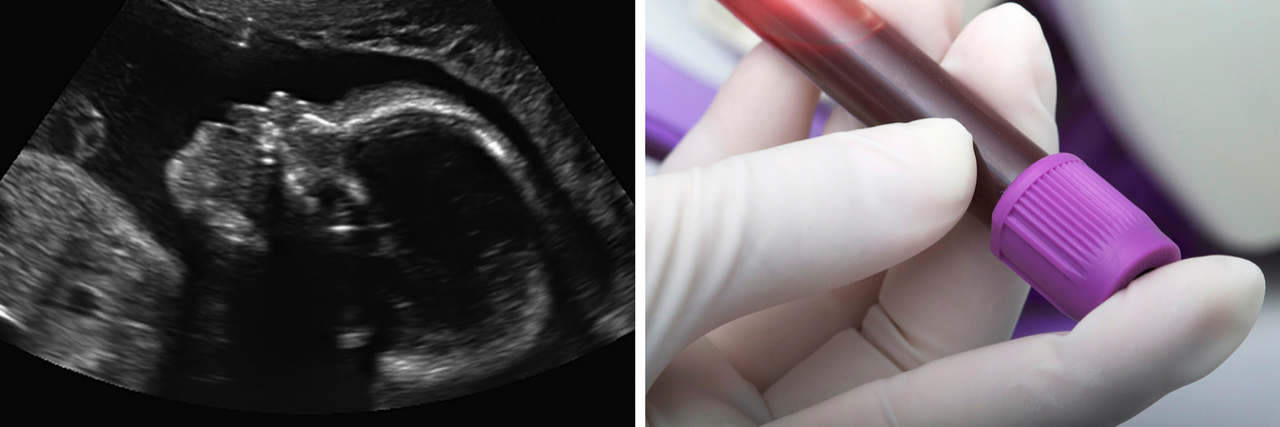

1. One study suggests a correlation between autism and ultrasounds.

On February 12, a new study about the possible link between autism and ultrasound usage during pregnancy came out. The study was published in JAMA Pediatrics by a team of researchers mostly from Boston Medical Center.

2. One study hints at a possible autism diagnostic blood test.

Another study, published February 19 in “Molecular Autism,” suggests researchers have taken the first steps to having a possible diagnostic test for autism. Autism is currently diagnosed by clinicians based primarily on behavioral and social development assessments. A biological diagnostic test does not exist.

The study was conducted by a team of researchers from the University of Warwick in England and the University of Bologna in Italy. This study had a small size of participants (69 total; 38 on the spectrum), and the average age was 8 years old. The researchers analyzed blood and urine samples from each of the children. They found that children on the spectrum had higher levels of damage to certain proteins in the plasma compared to the control set of children.